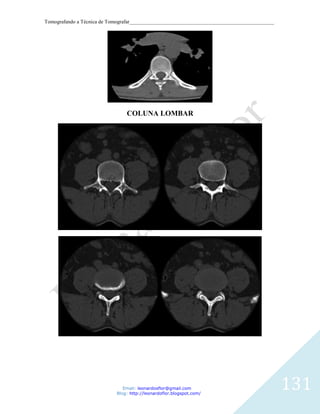

RECONSTRUCOES CORONAL E SAGITAL.